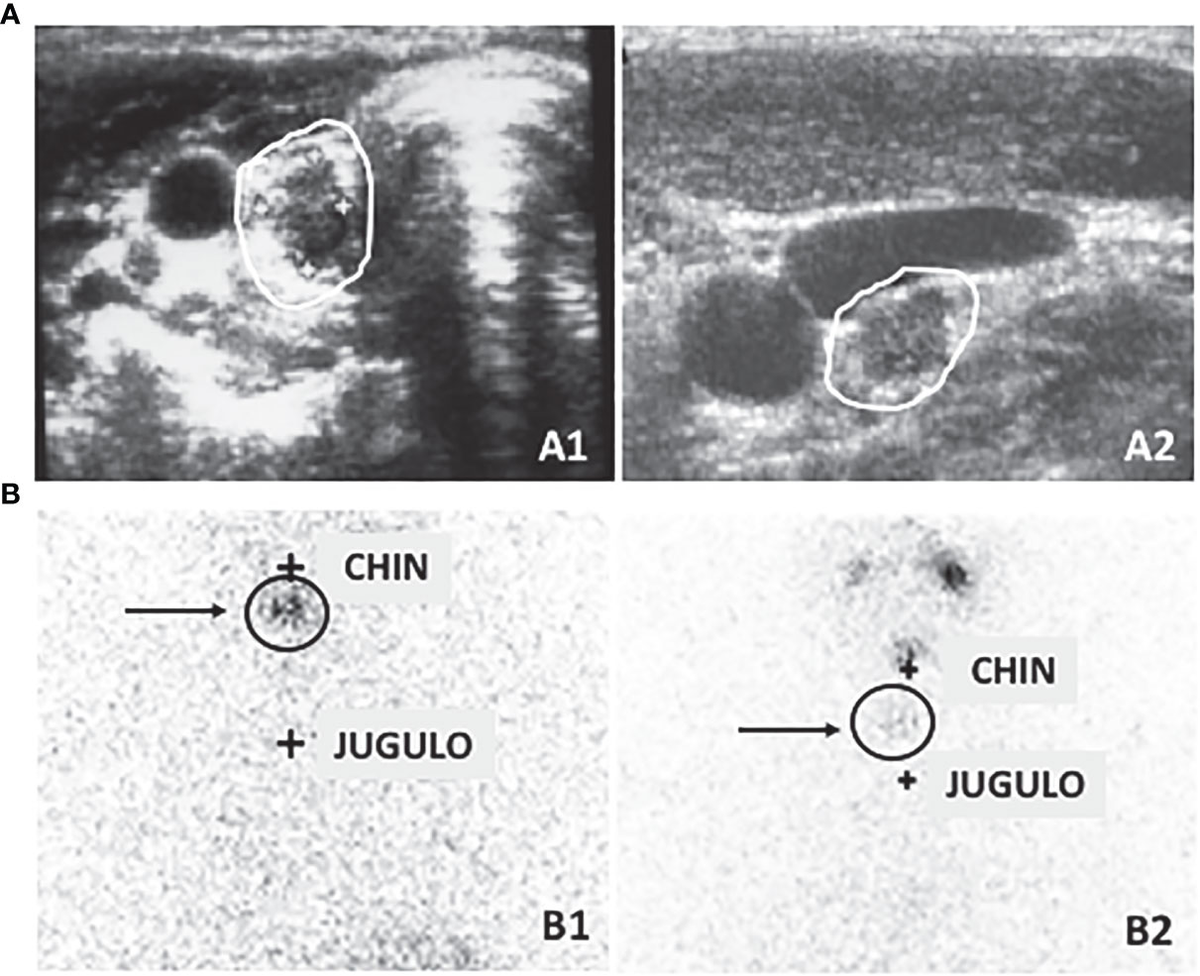

Thyroid Cancer Explore vol.1 no.2(2015 「Thyroid Cancer Expl Advances in Functional Imaging of Differentiated Thyroid Cancerの詳細情報

Advances in Functional Imaging of Differentiated Thyroid Cancer。Improving the diagnosis of thyroid cancer by machine。Frontiers | Active surveillance in differentiated thyroid。

ThyroidCancerExploreVol.1No

「ThyroidCancerExpl

ThyroidCancerExploreVol.1No

「ThyroidCancerExpl